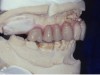

Figure 4. Occlusal contacts occur generally on the posterior teeth, most often on the first molars, followed by the second molars and premolars.

Figure 4